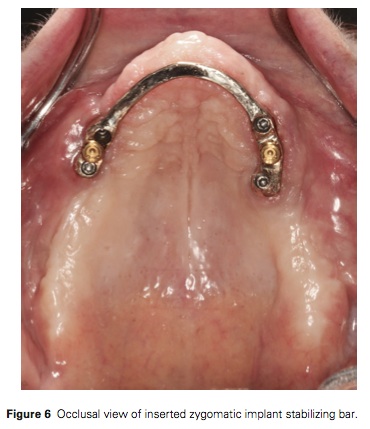

這個case report是在一個在上顎有種五隻植體做overdenture但是後來骨頭因為osteoporosis, 加上Alendronate (Fosamax)藥物, 導致上顎的植體都失敗了. 所以後來是在兩側各種兩隻zygomatic implant, 然後splinting bar, 上面再加兩個locator來給予retention, 而bar在製作過程中就墊一層蠟片, 避免未來denture會碰到bar. 所以植體主要是提供那兩個locator的retention而已. 我不太能了解為什麼denture要開窗, 除此之外的製作過程都算合理.